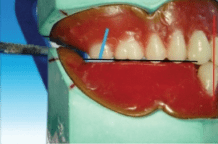

The buccal cusp of the maxillary second premolar corresponds with the buccal cusp of maxillary first premolar (blue line), and the palatal cusps of both the premolars correspond to the previous drawn line

Occlusal plane: Both buccal cusp and palatal cusp is in contact

with occlusal plane